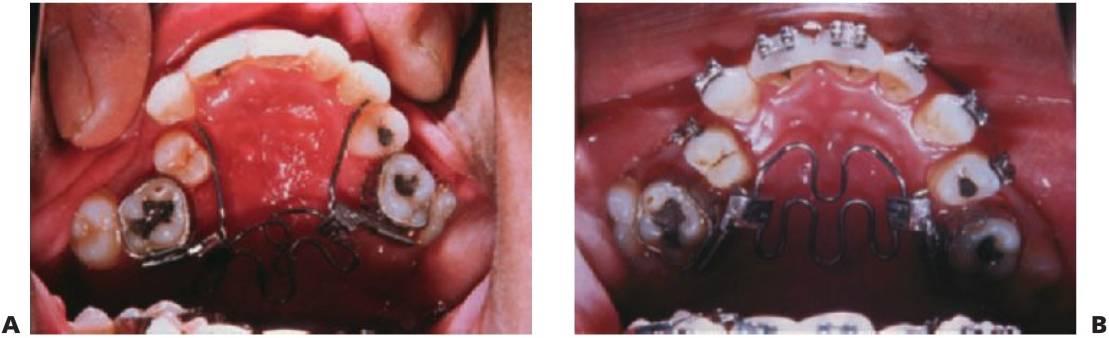

Expansión maxilar lenta: quad hélix/expansores de níquel-titanio

El quad hélix se ajusta a las bandas molares que se cementan en los primeros molares permanentes.

El dentista controla la activación del aparato.

La reactivación se realiza en visitas alternas y se puede realizar de forma intraoral mediante el uso de un alicate de tres puntas o extrayendo el aparato de la boca y realizando la expansión a mano.

La expansión debería proseguir hasta sobrecorregir los molares y se mantendría el aparato de esa forma durante 3 meses más. Así, la mordida cruzada suele corregirse en 4-6 meses.

El quad hélix puede utilizarse al mismo tiempo que la aparatología fija.

Los expansores de níquel-titanio precisan menos ajuste que los quad hélix convencionales de acero inoxidable.

Producen una cantidad predeterminada de expansión.

El enfriamiento del expansor permite constreñirlo e insertarlo en los tubos linguales de los molares superiores.

Cuando se calienta a la temperatura corporal, se convierte en elástico y ejerce una fuerza continua en los dientes que provoca la expansión de arco.

Las fuerzas de expansión producen también la desrotación simultánea de los molares (figs. 11.14, 11.15).